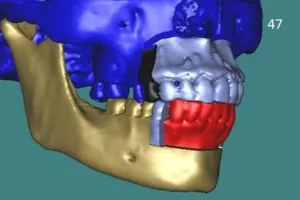

Les ostéotomies segmentaires.

Le chirurgien libère un segment (un fragment) du squelette alvéolaire qui contient les dents. Il n’existe pas d’interruption de continuité de la « base » osseuse du maxillaire ou de la mandibule.

L’ostéotomie segmentaire maxillaire antérieure et l’ostéotomie segmentaire mandibulaire antérieure.

Elles permettent de déplacer le bloc incisif et canin du maxillaire et de la mandibule dans toutes les directions souhaitées.

L’ostéotomie segmentaire maxillaire postérieure et l’ostéotomie segmentaire mandibulaire postérieure.

Uni ou bilatérale, elle permet de déplacer le bloc postérieur du maxillaire supérieur ou de la mandibule(bloc prémolo-molaire).